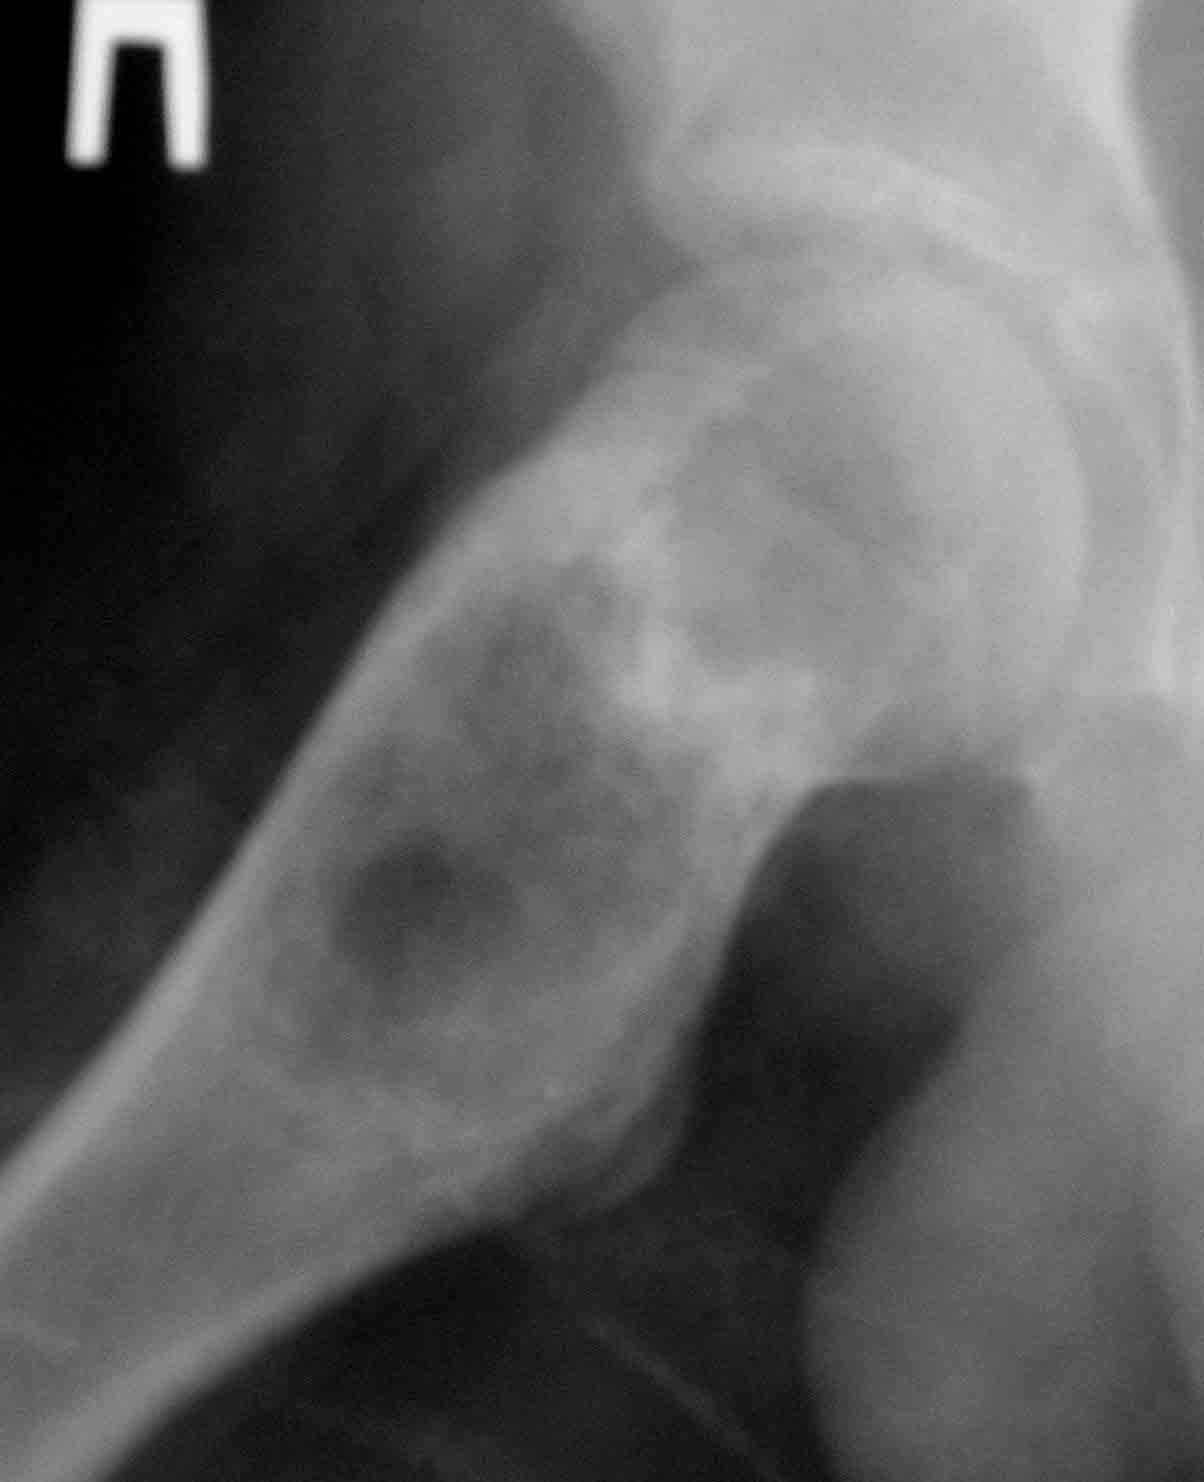

Дабы не уводить в офтопик вопрос о несросшемся переломе бедра, хочу добрым словом упомянутьколлапан - доступный и эффективный российский продукт, который судя по публикациям на форуме не нашел еще должного распространения в повседневной практике. Чтобы не быть обвиненным в рекламе или личной заинтересованности скажу, что работаю я в Казахстане, где большинство последних российских разработок не прошло регистрацию( отдельный вопрос почему?) и коллапан завозят родственники пациентов из соседних сибирских городов. За тридцать лет практики многократно возникали ситуации в которых остро чувствовалась проблема материала для заполнения костных дефектов- от открытых переломов до дефектов при секвестрэктомиии и удаления кистозных опухолей. Риск аутопластики в инфицированную среду или дефицит донорской кости у детей, повсеместное закрытие лабораторий консервации тканей, высокая стоимость зарубежных остеоиндуктивных материалов делают коллапан одним самых доступных материалов в exUSSR \простите за пафос\. В нашем отделении мы применяем коллапан в гранулах с антибиотиком для пристеночной пластики при удалении секвестров при послеоперационных и посттравматических остеитах, при остеосинтезе ложных суставов и заполнении костных дефектов. Коллапан не может применяться в ситуациях где имплантату необходима опорная функция, но это уже другая песня. Привожу пример 15 летнего пациента с обширной фиброзной дисплазией проксимального бедра, которого я оперирован в ноябре 2005, контрольный снимок от 3-2006.

Произведена подвертельная трепанация, кюретаж и рыхлое заполнение гранулами коллапанаГ полости, ушло до 100 куб см гранул. Иммобилизация не проводилась, нагрузка на ногу разрешения через 5 мес, сейчас подросток активно отдыхает на каникулах. Аваскулярный некроз головки вроде не предвидится, думается, что в процессе роста кисты коллатеральное кровообращение сформироваласьдостаточно, о судьбе ростковой зоны можно будет говорить через год. Кстати в одном НИИ ему былапредложена операция эндопротезирования. Первые 2 мес

мне, старому провинциальному врачу, трудно с позиций доказательной медицины дискутировать с Вами, да и не это цель моей реплики.Хотелось лишь показать, что на сегодняшний у российских ортопедов есть доступный повсюду недорогй материал, о котором и не мечталось десяток лет назад. Пример, который я привел, иллюстрировал мои эмоции, которые я испытал, увидя снимки через 3 месяца- на месте пустоты выросла костная ткань. Насколько органотипична она судить не могу, но 4 года и десяток наблюдений с энхондромами на пальцах убедительны\для меня\ Антибиотик выделяется 3 недели, по данным разработчиков. Каждый делает выбор сам, но все же опыт коллег более достоверен, чем публикации в брошюрахх, полученных у стендов выставок.

Под рукой нашелся повод для похожих эмоций. Патологический перелом на месте рецидива костной кисты у девочки 16 лет (обсуждали этот случай

года два назад). Ни коллапана, ни трансплантатов, ничего другого в очаг не вводили, кроме нержавеющей стали. Она, видимо, тоже остеоиндуктор - видно, что на месте пустоты через несколько месяцев кость.

Согласен на все сто с Вашей последней фразой. Не знаю как учат сейчас врачей в ВУЗАХ, но по-моему основы доказательной медицины познаются уже в процессе работы. А что касается Вашего примера, то давно известно, что кистозные опухоли у детей могут спонтанно регенерировать после перелома. Пример рецидива кисты после неадекватной пластики Вы видите на этой же странице. По поводу РФ не могу судить, но в Казахстане больше применяют стоматологи для подготовки к импланатации протезов при дефектах костей челюсти. Спасибо за обсуждение темы.